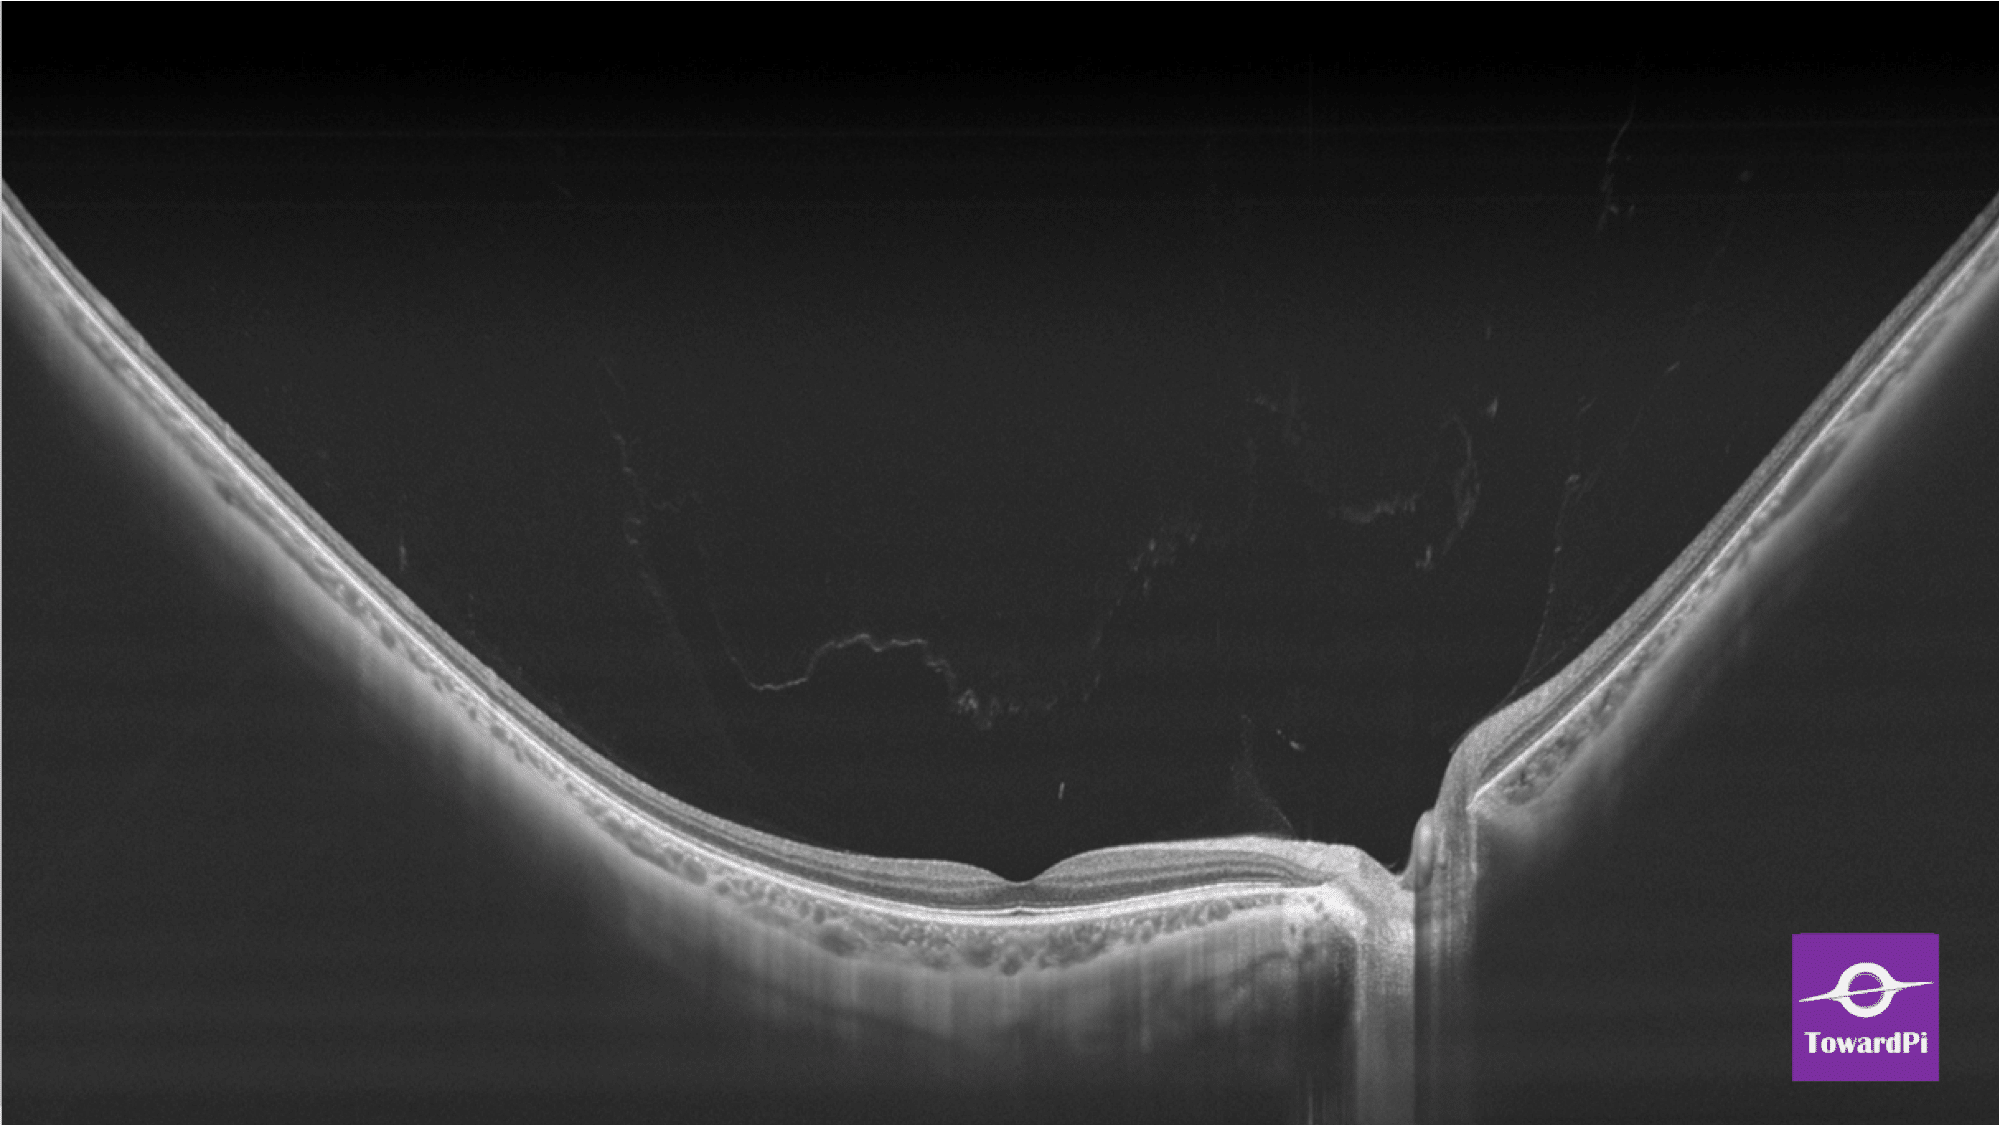

- Full-Range wide-field Swept Source OCT

- HD Anterior Scan with Anterior OCTA